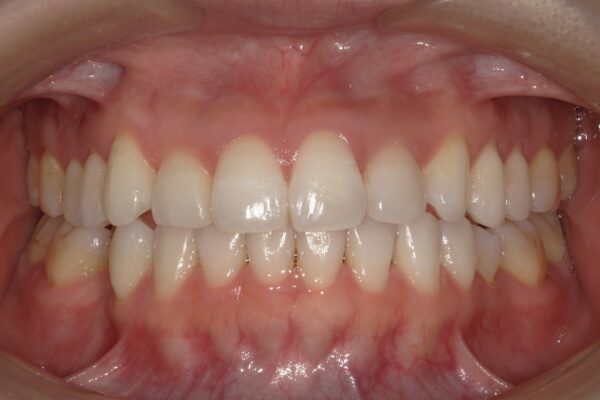

Images